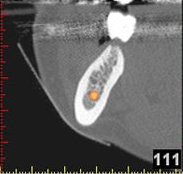

Auf Basis einer computertomografischen (CT-) Kieferaufnahme ist eine dreidimensionale Darstellung der Knochen möglich. Der Zahnarzt kann dann am Computerbildschirm die Knochenqualität (z. B. Knochendichte) beurteilen und die optimale Position der Implantate im Vorfeld planen. Durch Verwendung spezieller Röntgenschablonen lässt sich auch die erwünschte Zahnstellung in die Planung einbeziehen. Die Simulation der OP erlaubt, das zu erwartende Ergebnis mit größtmöglicher Sicherheit vorherzusagen und dem Patienten am Bildschirm zu veranschaulichen.

(siehe Bild 3 und 4).

Mit diesen gewonnenen Informationen und Planungen stellt der Zahnarzt interaktiv spezielle Bohrschablonen her. Diese ermöglichen eine exakte Positionierung der Implantate, so wie vorher am Computer geplant.